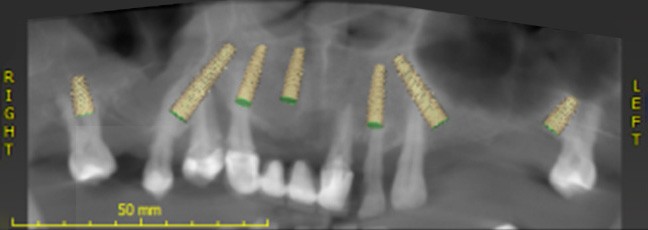

Dzięki cyfrowej implantologii możliwe jest wykonanie precyzyjnego skanu jamy ustnej oraz dokładne zaplanowanie położenia implantów dentystycznych, także względem siebie nawzajem. Pozwala to na przygotowanie indywidualnych szablonów chirurgicznych gwarantujących prawidłowe i bezpieczne umieszczenie implantów w kości, a także zaprojektowanie prac protetycznych. Jeszcze przed rozpoczęciem leczenia pacjent otrzymuje wizualizację planowanego efektu końcowego.

Dzięki nowoczesnym technologiom cyfrowym, zaawansowanej diagnostyce i precyzyjnemu planowaniu umożliwiamy kompleksową odbudowę uzębienia, w tym natychmiastową rekonstrukcję braków zębowych. Stosujemy procedury chirurgiczne o minimalnej inwazyjności, co pozwala znacząco ograniczyć dyskomfort pozabiegowy.

Pacjenci doceniają Naturaldens za indywidualne podejście, wykorzystanie najnowszych rozwiązań technologicznych zwiększających precyzję i bezpieczeństwo zabiegów, najwyższej jakości materiały oraz pełną dostępność diagnostyki na miejscu, w tym tomografii komputerowej CBCT.